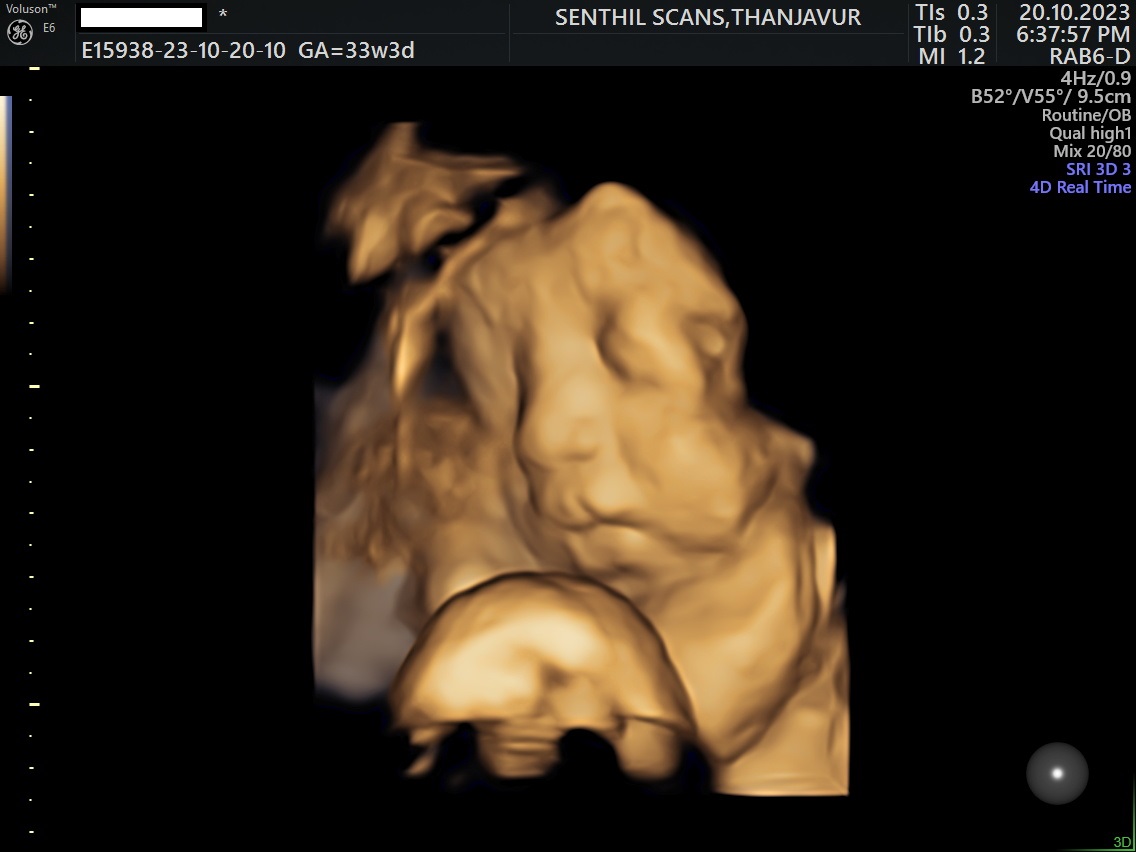

Ultrasound Scan